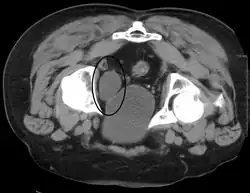

Urinary bladder (black butterfly-like shape) and hyperplastic prostate (BPH) visualized by medical ultrasound

Frequent urination can be due to excessive urine production, small bladder capacity, irritability or incomplete emptying. Males with an enlarged prostate urinate more frequently. One definition of an overactive bladder is when a person urinates more than eight times per day.[28] An overactive bladder can often cause urinary incontinence. Though both urinary frequency and volumes have been shown to have a circadian rhythm, meaning day and night cycles,[29] it is not entirely clear how these are disturbed in the overactive bladder. Urodynamic testing can help to explain the symptoms. An underactive bladder is the condition where there is a difficulty in passing urine and is the main symptom of a neurogenic bladder. Frequent urination at night may indicate the presence of bladder stones.